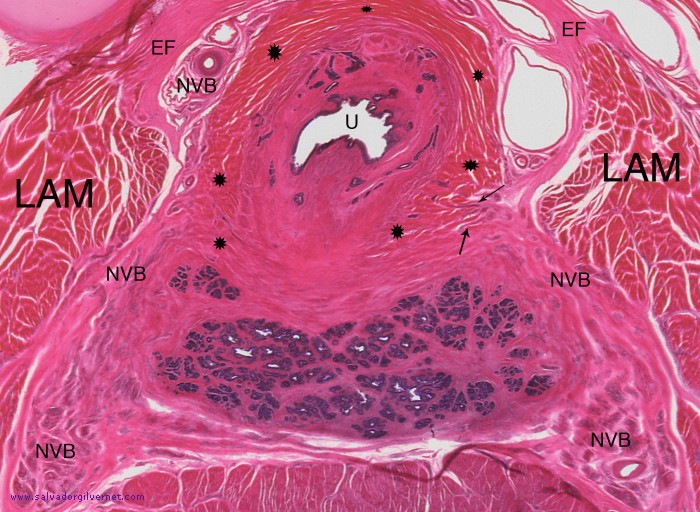

Detalle 2: Hoja visceral de la fascia endopélvica (EF). Haces neurovasculares (NVB). Esfínter uretral externo (asteriscos). Uretra prostática inframontanal (U). Músculo elevador del ano (LAM). Fibras nerviosas del haz neurovascular derecho dando ramas que penetran en el esfínter uretral externo (flechas).

Pelvis fetal varón (8 meses)

• Sección transversal oblícua a nivel de la uretra prostática inframontanal

Tinción HE

Ramas isquiopubianas. Ligamento de Henle. Plexo venoso de Santorini. Fascia endopélvica (1). Uretra prostática inframontanal rodeada por las fibras del esfínter uretral externo. Próstata. Haces neurovasculares. Recto. Músculo elevador del ano (2).